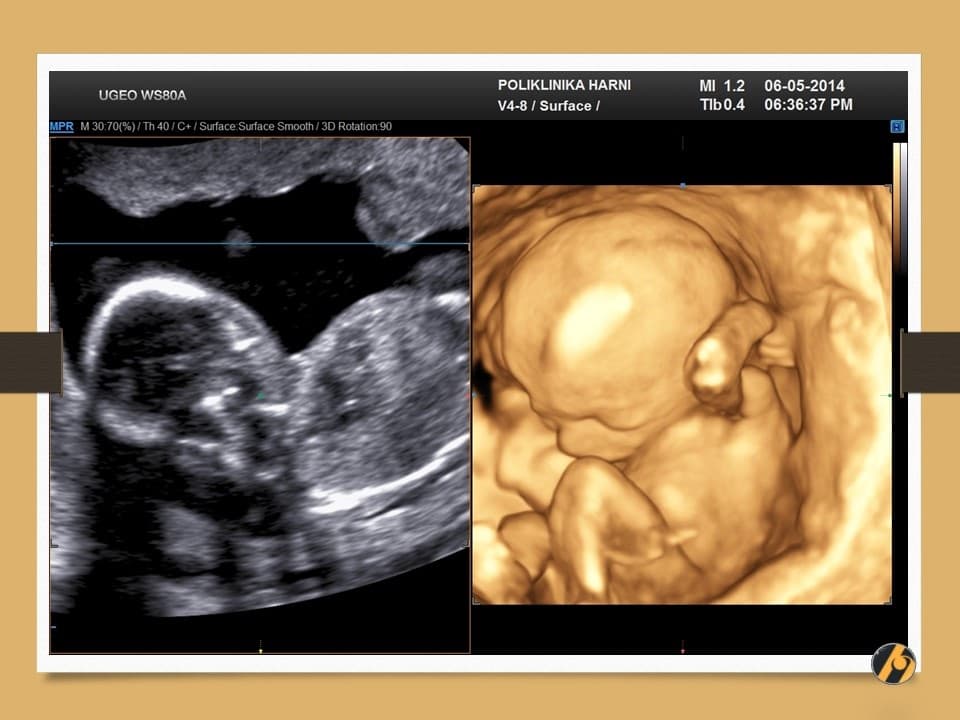

Nastavlja se finiji razvitak kože vaše bebe, koja je u ovo vrijeme tanka i prozirna i kroz koju se vidi mnoštvo krvnih žilica. Lanugo dlačice prekrivaju gotovo cijelu površinu kože bebe, a jasnije se ističu dlačice na obrvama. Počinje rasti kosa na glavi, a pigmentne stanice počinju stvarati crni pigment.

Razvijaju se daljnji centri okoštavanja i kosti, kao i koštana moždina koja preuzima funkciju žumanjčane vreće u stvaranju krvi djeteta. Zglobovi bebe su sve pokretljiviji, a beba s time i sve savitljivija. Sada vaša beba može svoje prstiće stisnuti u šaku.

Vaša beba guta amnijsku tekućinu koja ga okružuje, što pomaže sazrijevanju respiratornog sustava. Bebine oči su i dalje zatvorene, ali beba počinju reagirati na svjetlost izvan vaše maternice. Od ovog tjedna vaše će dijete početi čuti zvukove u vašem tijelu, poput otkucaja srca i trbuha.

Vaša beba dugačka je 10 - 12 cm, a teška 50 - 100 g.